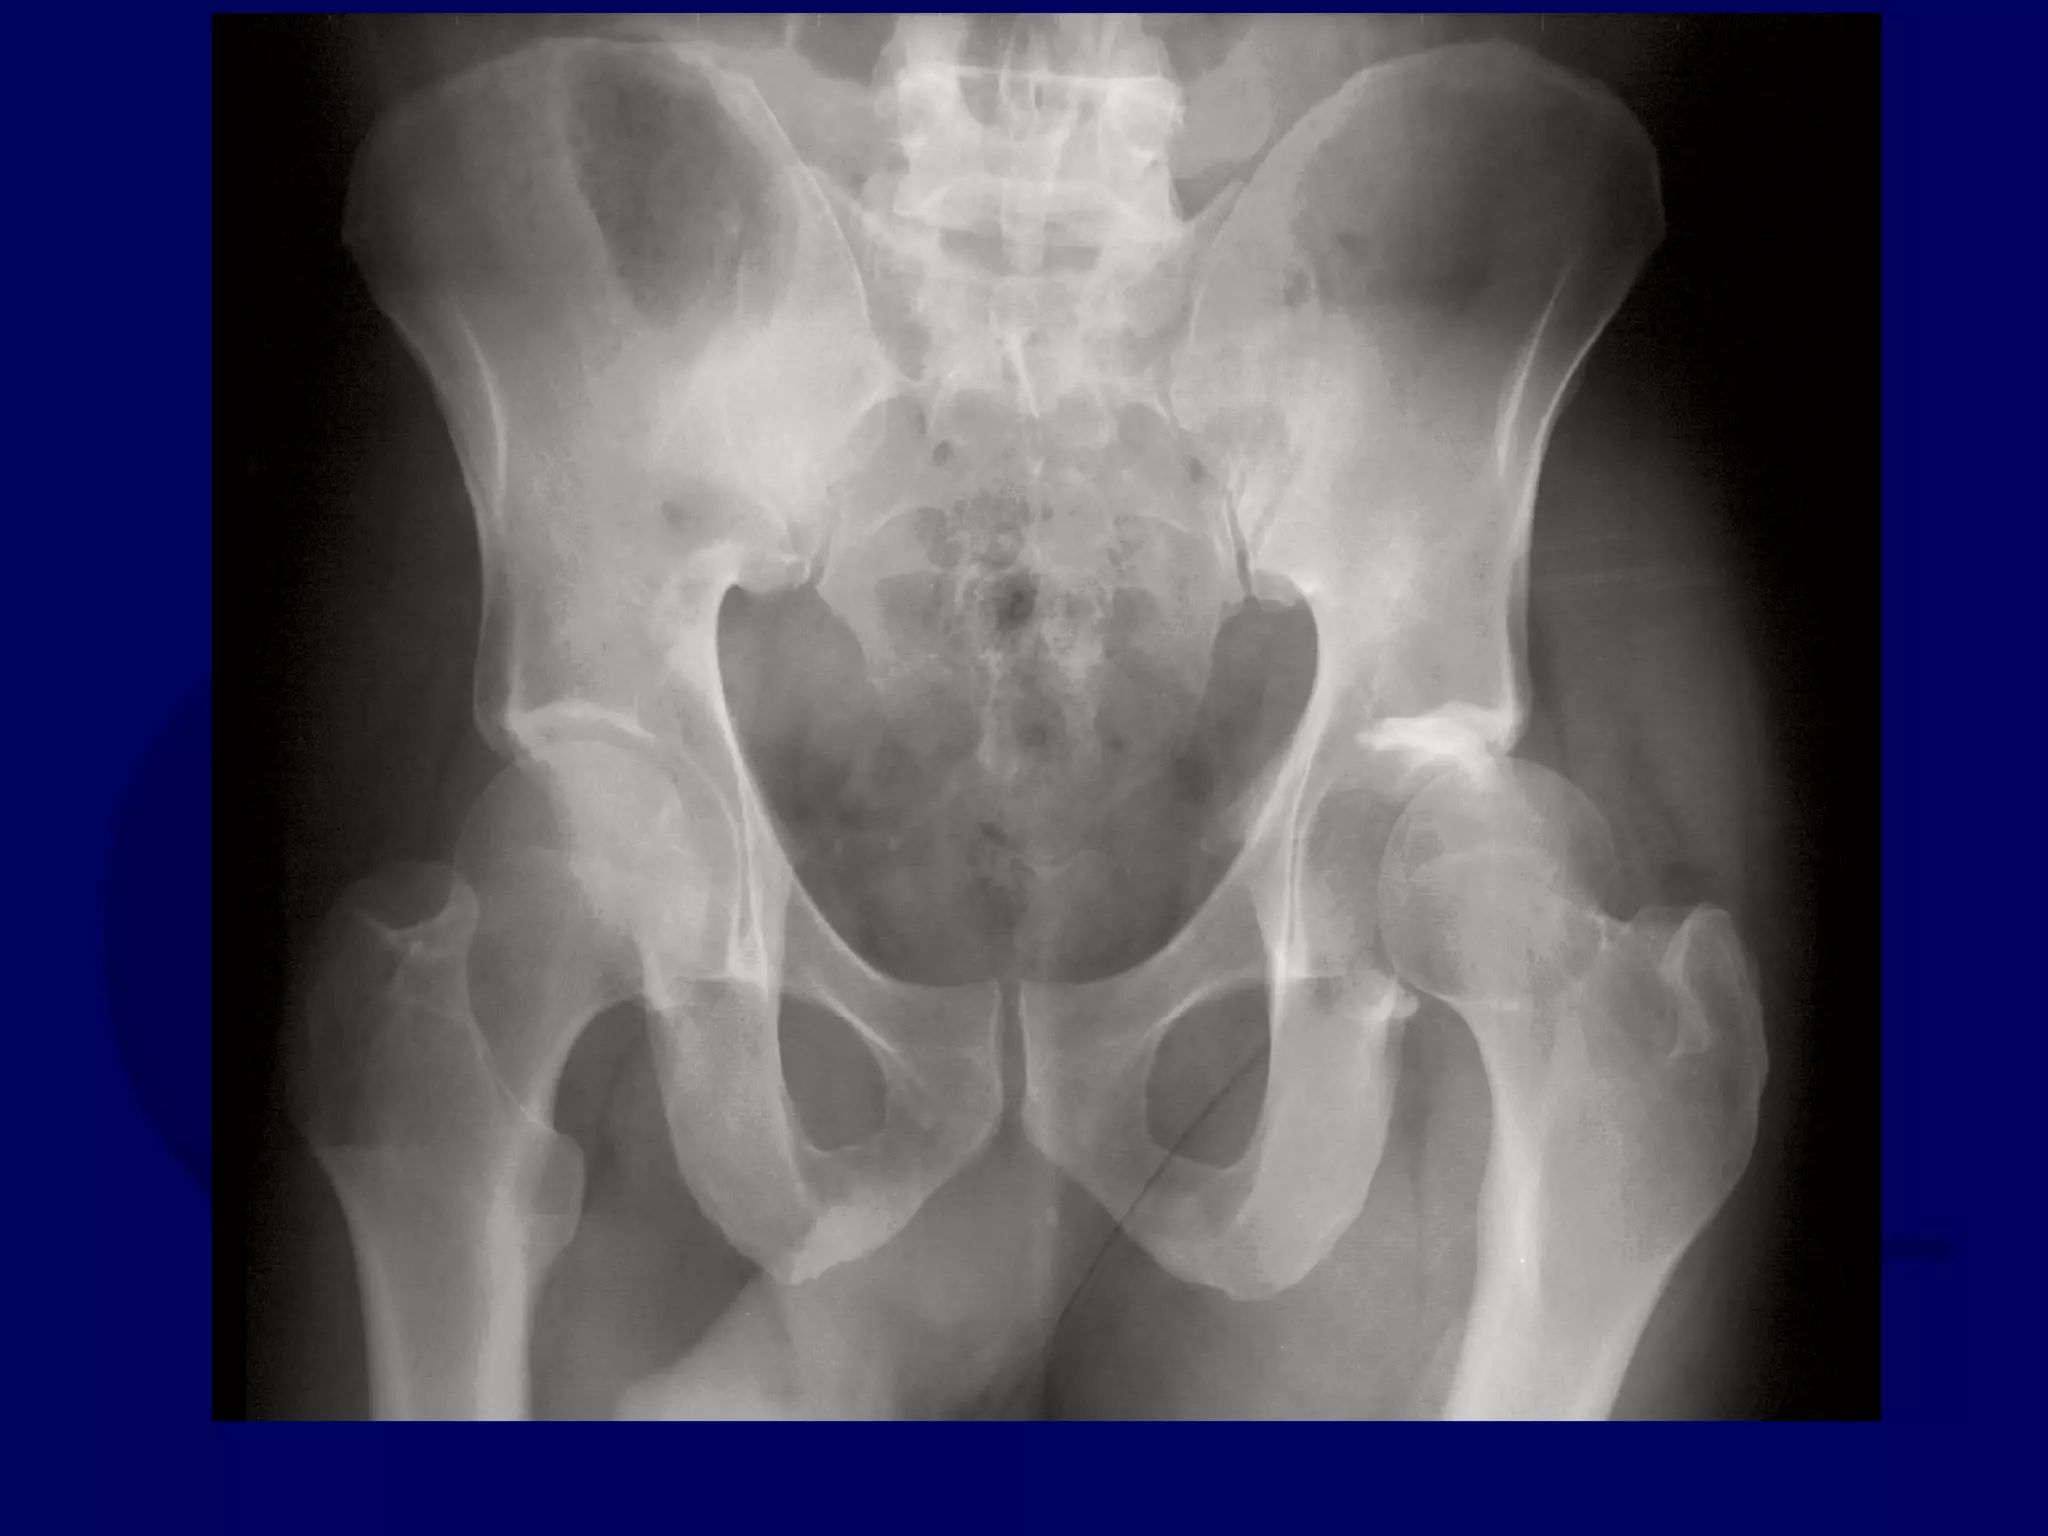

Both Column

Acetabular Fracture

18 Y.O. Female

Isolated Injury

R.C. 00.03.09

SPUR

SIGN